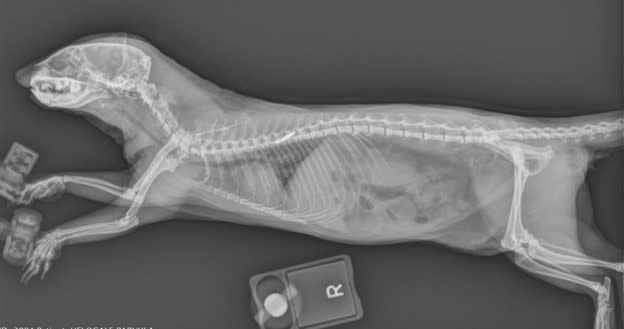

Zoo and Aquarium Radiology Database

The Zoo and Aquarium Radiology Database helps veterinary professionals use diagnostic imaging to improve animal care, support wildlife conservation, and advance research.

Radiology Consulting Service

Brookfield Zoo Chicago’s Radiology Consulting Service helps veterinarians worldwide provide advanced medical care for zoo and aquarium animals, improve diagnostic imaging, and support conservation efforts.